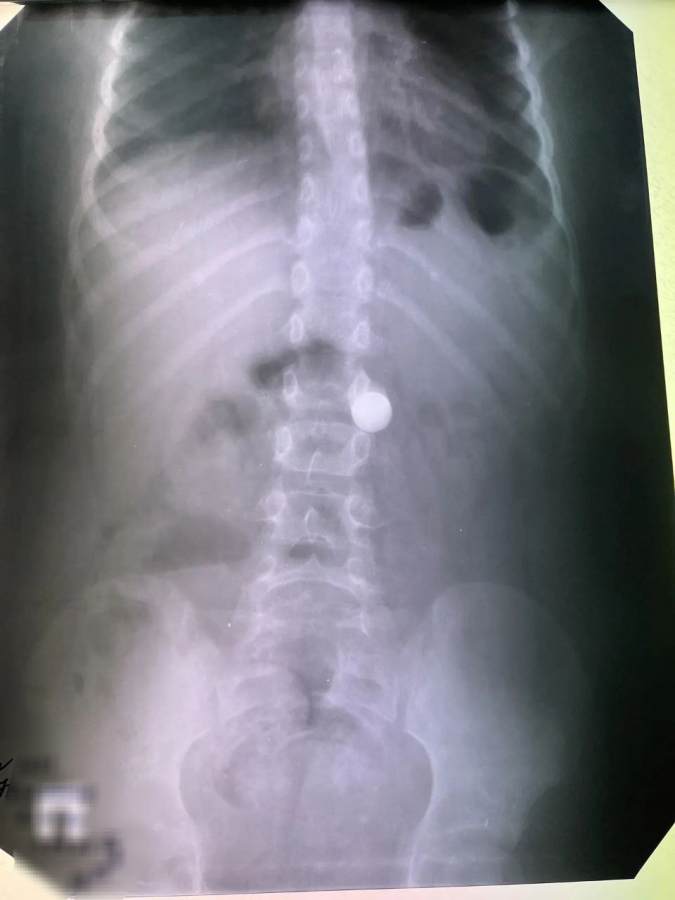

В Балакове Саратовской области 8-летний мальчик проглотил увесистый металлический шарик. Об этом рассказали в пресс-службе Балаковской городской клинической больницы.

Как правило, в новогодние праздники врачи-эндоскописты городской больницы сталкиваются с потоком пациентов, которые случайно проглотили монеты, детали конструктора или косточки. За прошедшие каникулы поступил мальчик, который проглотил увесистый металлический шарик диаметром в сантиметр. К счастью, других подобных случаев за праздничные дни не зафиксировано.